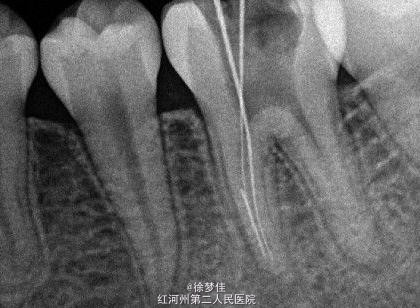

左下6近中根管断针X-P,断针长度约4MM, 根尖慢性炎症

插针确定断针根管,为近舌根管,插针有阻力,EDTA封存一周复诊。打开根管上部通路,根管大量清洗剂等冲洗,找到后,直接用超声根管搓15号带出断针。